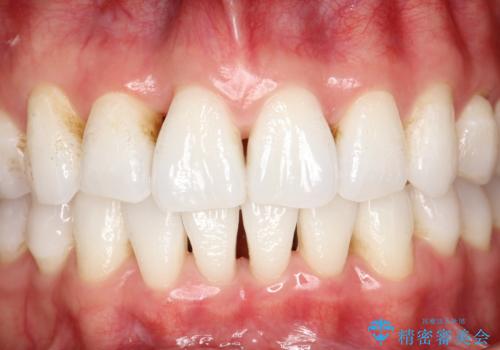

インビザライン終了時のPMTC

PMTC60分1万円+tax(保険適応外)を行いました。

インビザライン矯正治療は、歯にアタッチメント(歯を動かすための突起物)をつけます。そのため、矯正治療が終了し、アタッチメントを外すと着色が目立つことがあります。矯正治療の終了のタイミングではクリーニングを行い、着色の除去や歯と歯の間・歯と歯肉との境目などのケアをしっかりすることをおすすめしています。